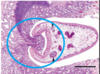

- Locate in the wall of the duodenum and the abomasum

- Mechanic action/trauma by posterior sucker and movement

- Erosion of the intestinal villi

- Antigenic activity -> acute inflammatory reaction

- Congestion and oedematous enteritis

- Erosions and petechiae surrounded by necrotic zone

- Atrophy of the villi